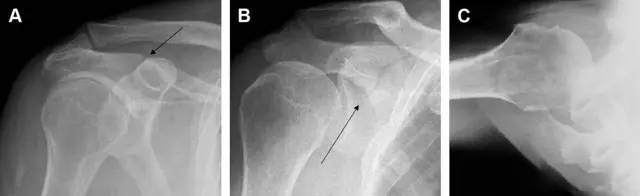

图 肩峰骨折。内旋位前后位(A)片上,骨折线几乎被喙突完全遮挡, 但是在标准前后位(B)和腋位(C)片上可见骨折线